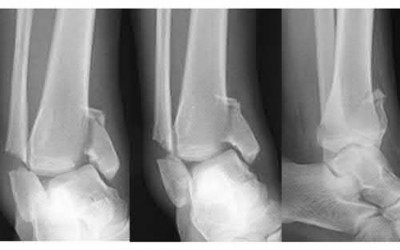

A 25-year-old male sustains an ankle fracture dislocation and undergoes open reduction and internal fixation. He returns to clinic five months following surgery complaining of continued ankle pain and instability with weight bearing. His immediate post-operative AP radiograph is seen in Figure A. Which of the following could have prevented this patient from developing persistent pain?

The patient presents with continued ankle pain and instability following open reduction and internal fixation. The radiograph in figure A demonstrates inadequate restoration of fibular length, likely leading to continued tibiotalar instability.

Illustration A demonstrates fibular malreduction with dislocation of the fibula anterior to the tibial incisura. Illustration B shows a comminuted fibula fracture along with a measurement of length from an intact fibula. The arc from the lateral process of the talus to the peroneal groove of the distal fibula is known as the "dime" sign and should remain unbroken if fibular length has been restored. Illustration C demonstrates the use of a push-pull screw and lamina spreader to regain length intraoperatively for a comminuted fibula fracture.

Chu and Weiner review management of malunions of the distal fibula. The authors state that restoration of fibular length, alignment and rotation leads to reduction of the talus, provides a buttress to talar motion in the setting of an incompetent deltoid, and allows the syndesmotic ligaments to heal at the appropriate tension.